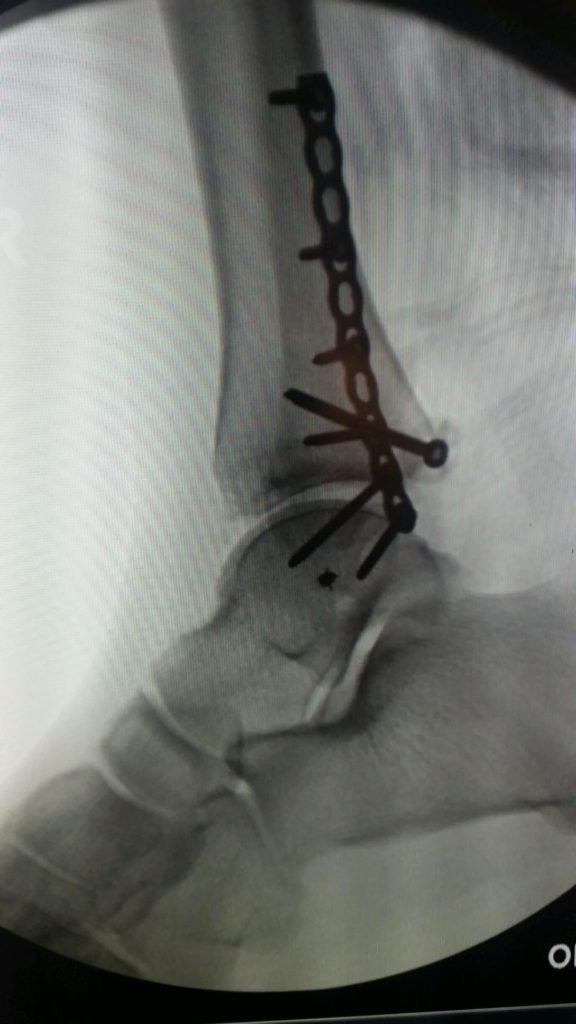

In October 2016 I was knocked over during a night out in New York City and dislocated and fractured my ankle. The following week, I went to HSS and met with Dr. Wellman. Right away he was very positive and optimistic with my options. He was able to fit me into his schedule four days later (10/24/2016) and inserted eight screws and a plate into my ankle. I have been going to PT at HSS for the past three months, seeing Erica Fritz. One month after surgery I was walking on my own without a boot or crutches. I am now able to walk and run without any pain! Thanks to everyone at HSS that has helped be get back on my feet so quickly!